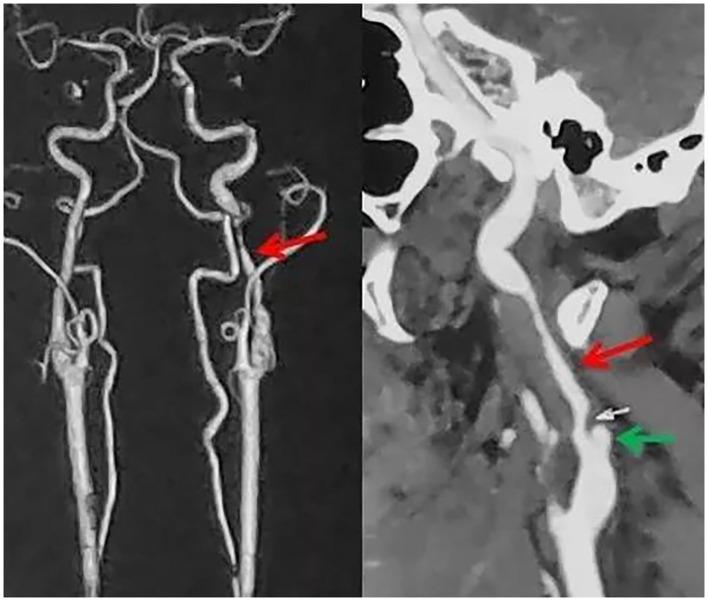

Internal carotid artery dissection (ICAD) results from a tear in the intima or rupture of the vasa vasorum with bleeding within the media resulting in separation of the vessel wall layers and a false lumen. It may cause arterial stenosis, occlusion, or dissecting pseudoaneurysm. Currently, the treatment of ICAD is controversial, including drug therapy and endovascular stent implantation. Simultaneous spontaneous dissection of bilateral carotid artery is rarely reported. We reported a 39-year-old-man with bilateral ICAD. Although the long-term durability of endovascular stent remains to be determined, for ICAD failed with active drug treatment and combined with hemodynamic impairment, early endovascular stent should be considered.

颈内动脉夹层(ICAD)是由于内膜撕裂或滋养血管破裂,血液在中膜内出血,导致血管壁各层分离并形成假腔。它可能导致动脉狭窄、闭塞或夹层假性动脉瘤。目前,ICAD的治疗存在争议,包括药物治疗和血管内支架植入。双侧颈动脉同时自发性夹层的报道很少。我们报告了一名39岁的双侧ICAD男性患者。尽管血管内支架的长期耐久性仍有待确定,但对于积极药物治疗失败且合并血流动力学损害的ICAD,应考虑早期进行血管内支架治疗。